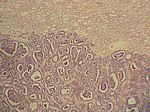

Wilms-Tumor, HE